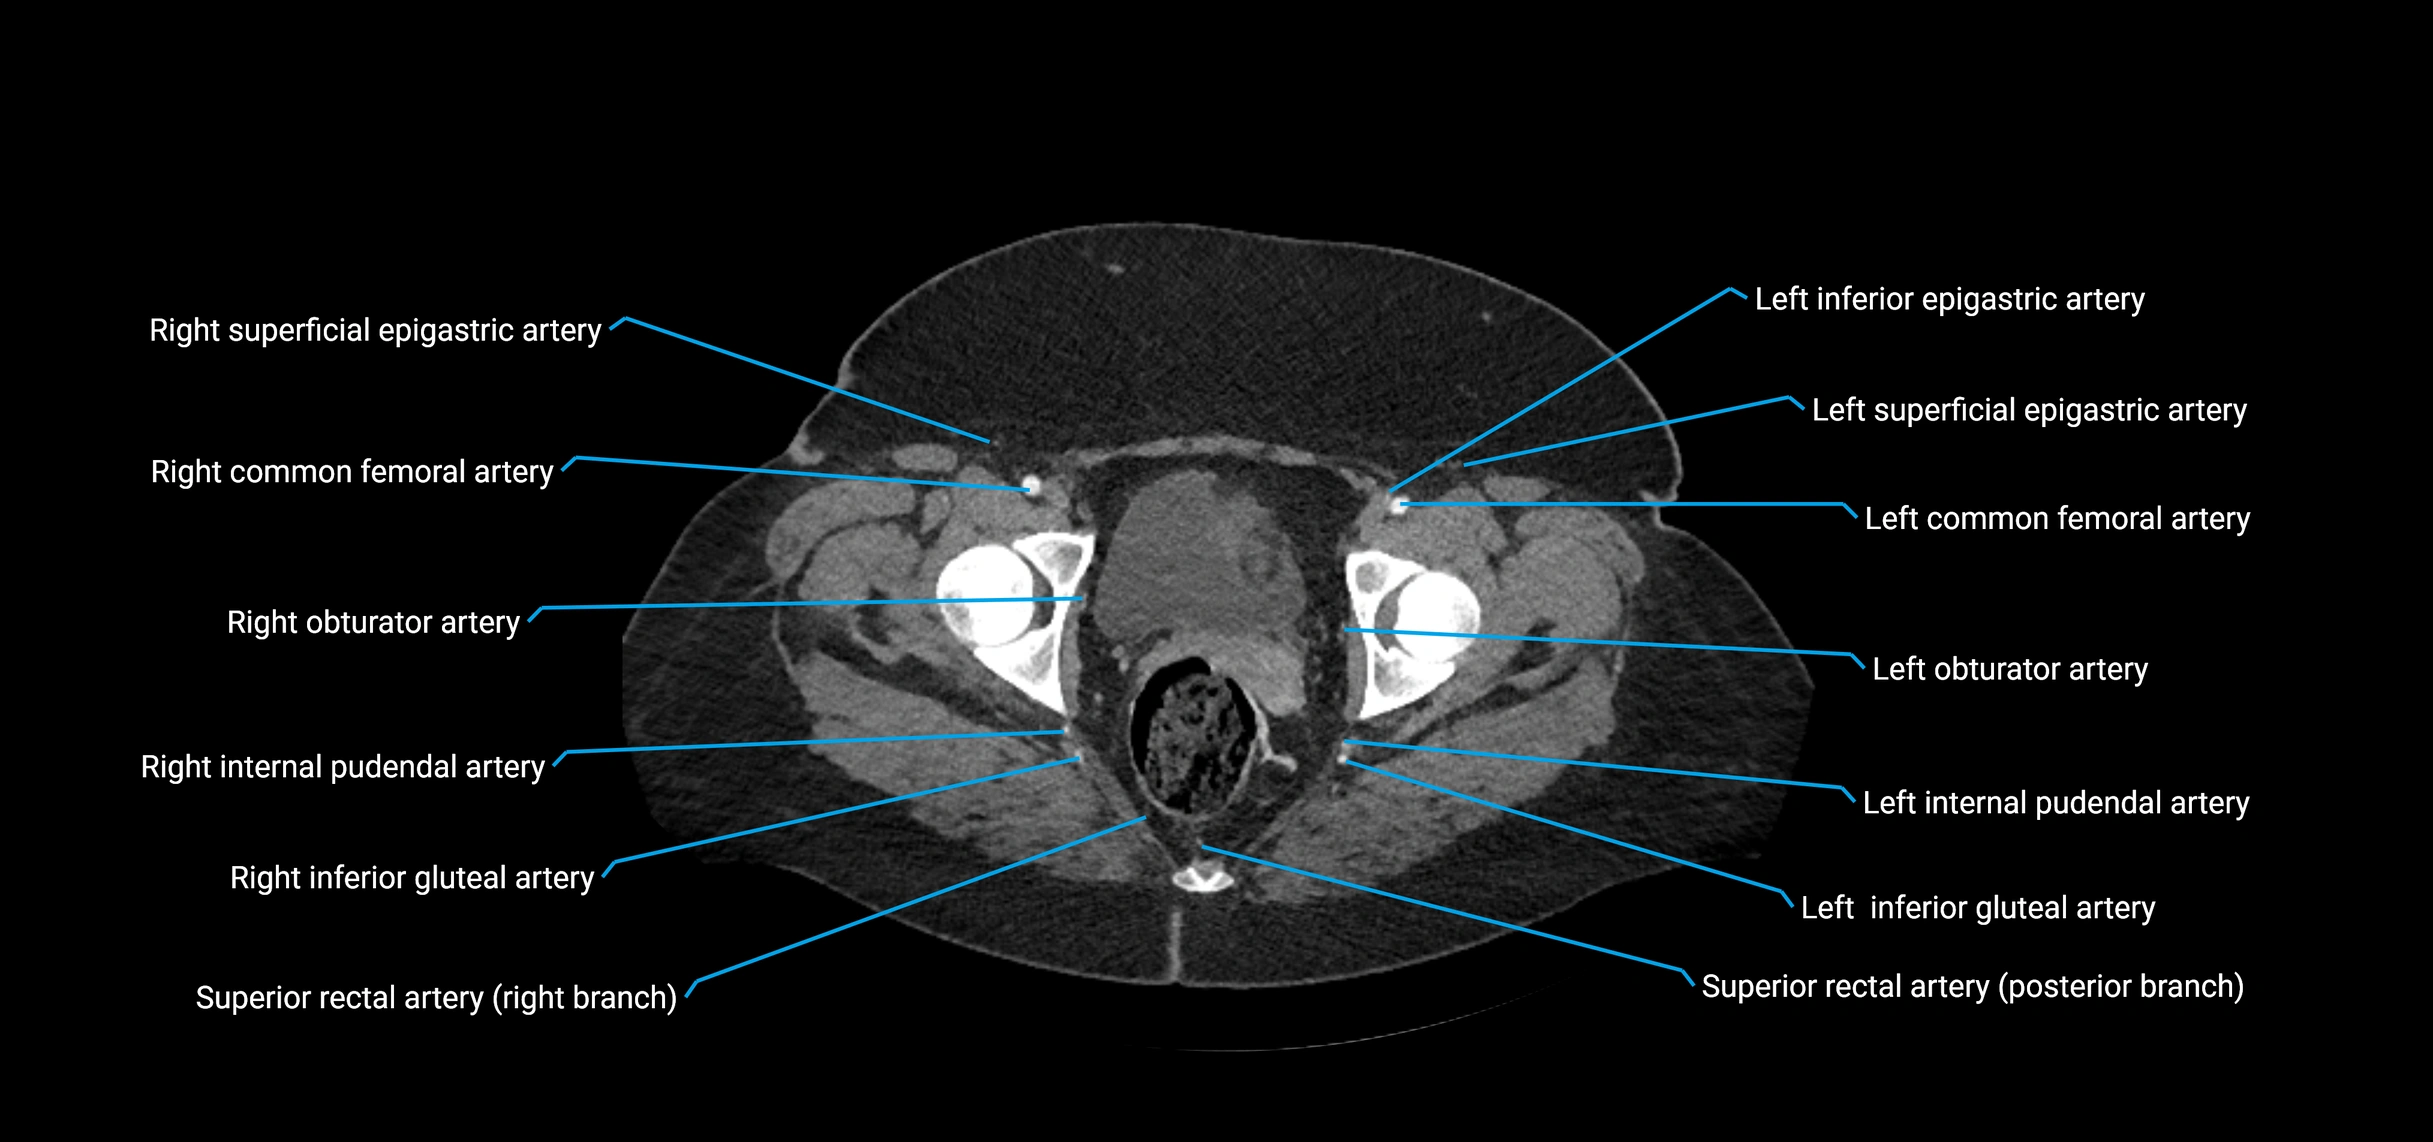

Contrast-enhanced CT (CTA):

• Gold standard for abdominal aortic imaging

• Provides excellent detail of lumen, wall, aneurysm, thrombus, and branch vessels

• Multiplanar and 3D reconstructions help in aneurysm measurement, stent graft planning, and dissection evaluation

• Detects acute rupture, traumatic injury, or occlusion with high sensitivity